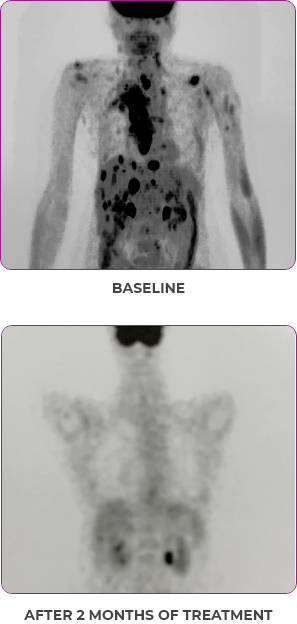

BASELINE

AFTER 2 MONTHS OF TREATMENT

56-YEAR-OLD FEMALE WITH MULTIPLE METASTASES3

PATIENT CASE:

METASTATIC, RAIa-REFRACTORY,

PAPILLARY THYROID CANCER1

- 56-year-old female with PTCa that had metastasized to multiple sites, including the brain

- Progression after first- and second-line systemic treatment

- PRa after 4 weeks on VITRAKVI® (larotrectinib); CRa after 8 weeks

- At last assessment, complete response was sustained over an 11-month period

Clinical presentation1

- Patient was assessed to have metastatic, rapidly progressive, RAl-refractory PTC based on imaging that revealed multiple metastatic sites, including the neck, mediastinum, lung, scalp, and bones

- Biopsy of a scalp lesion helped to confirm the PTC metastasis

- Metastases to the brain and liver were observed after progression on systemic treatments

VITRAKVI treatment1

- VITRAKVI 100 mg twice daily orally

Response to VITRAKVI1

- After 8 weeks on VITRAKVI, all target lesions had disappeared, demonstrating a complete response

- The complete response was sustained over 11 months of treatment with VITRAKVI

- Patient experienced Grade 1 fatigue and mild hepatic enzyme elevation

Response in primary and metastatic lesions1

MRIa imagery of the lungs. Arrow indicates large target lesion in left lung.1

SCAN 1: LUNG

MRIa imagery of the brain. Arrow indicates large target lesion in left lung.1

aMRI, magnetic resonance imaging.

Images courtesy of Dr Fabian Pitoia.